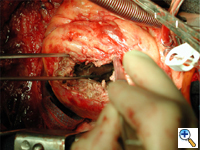

An anterolateral left ventriculotomy is made through the area of infarction parallel to and two centimeters away from the left anterior descending artery. Stay sutures can be placed through the edges of the ventriculotomy to maintain an open visual field. The interventricular septum, area of infarction, and site of rupture are visualized (Figure 3).

The necrotic portion of the septum is inspected but no debridement is necessary. The defect is not closed rather it is excluded from the ventricular cavity (Figure 4).